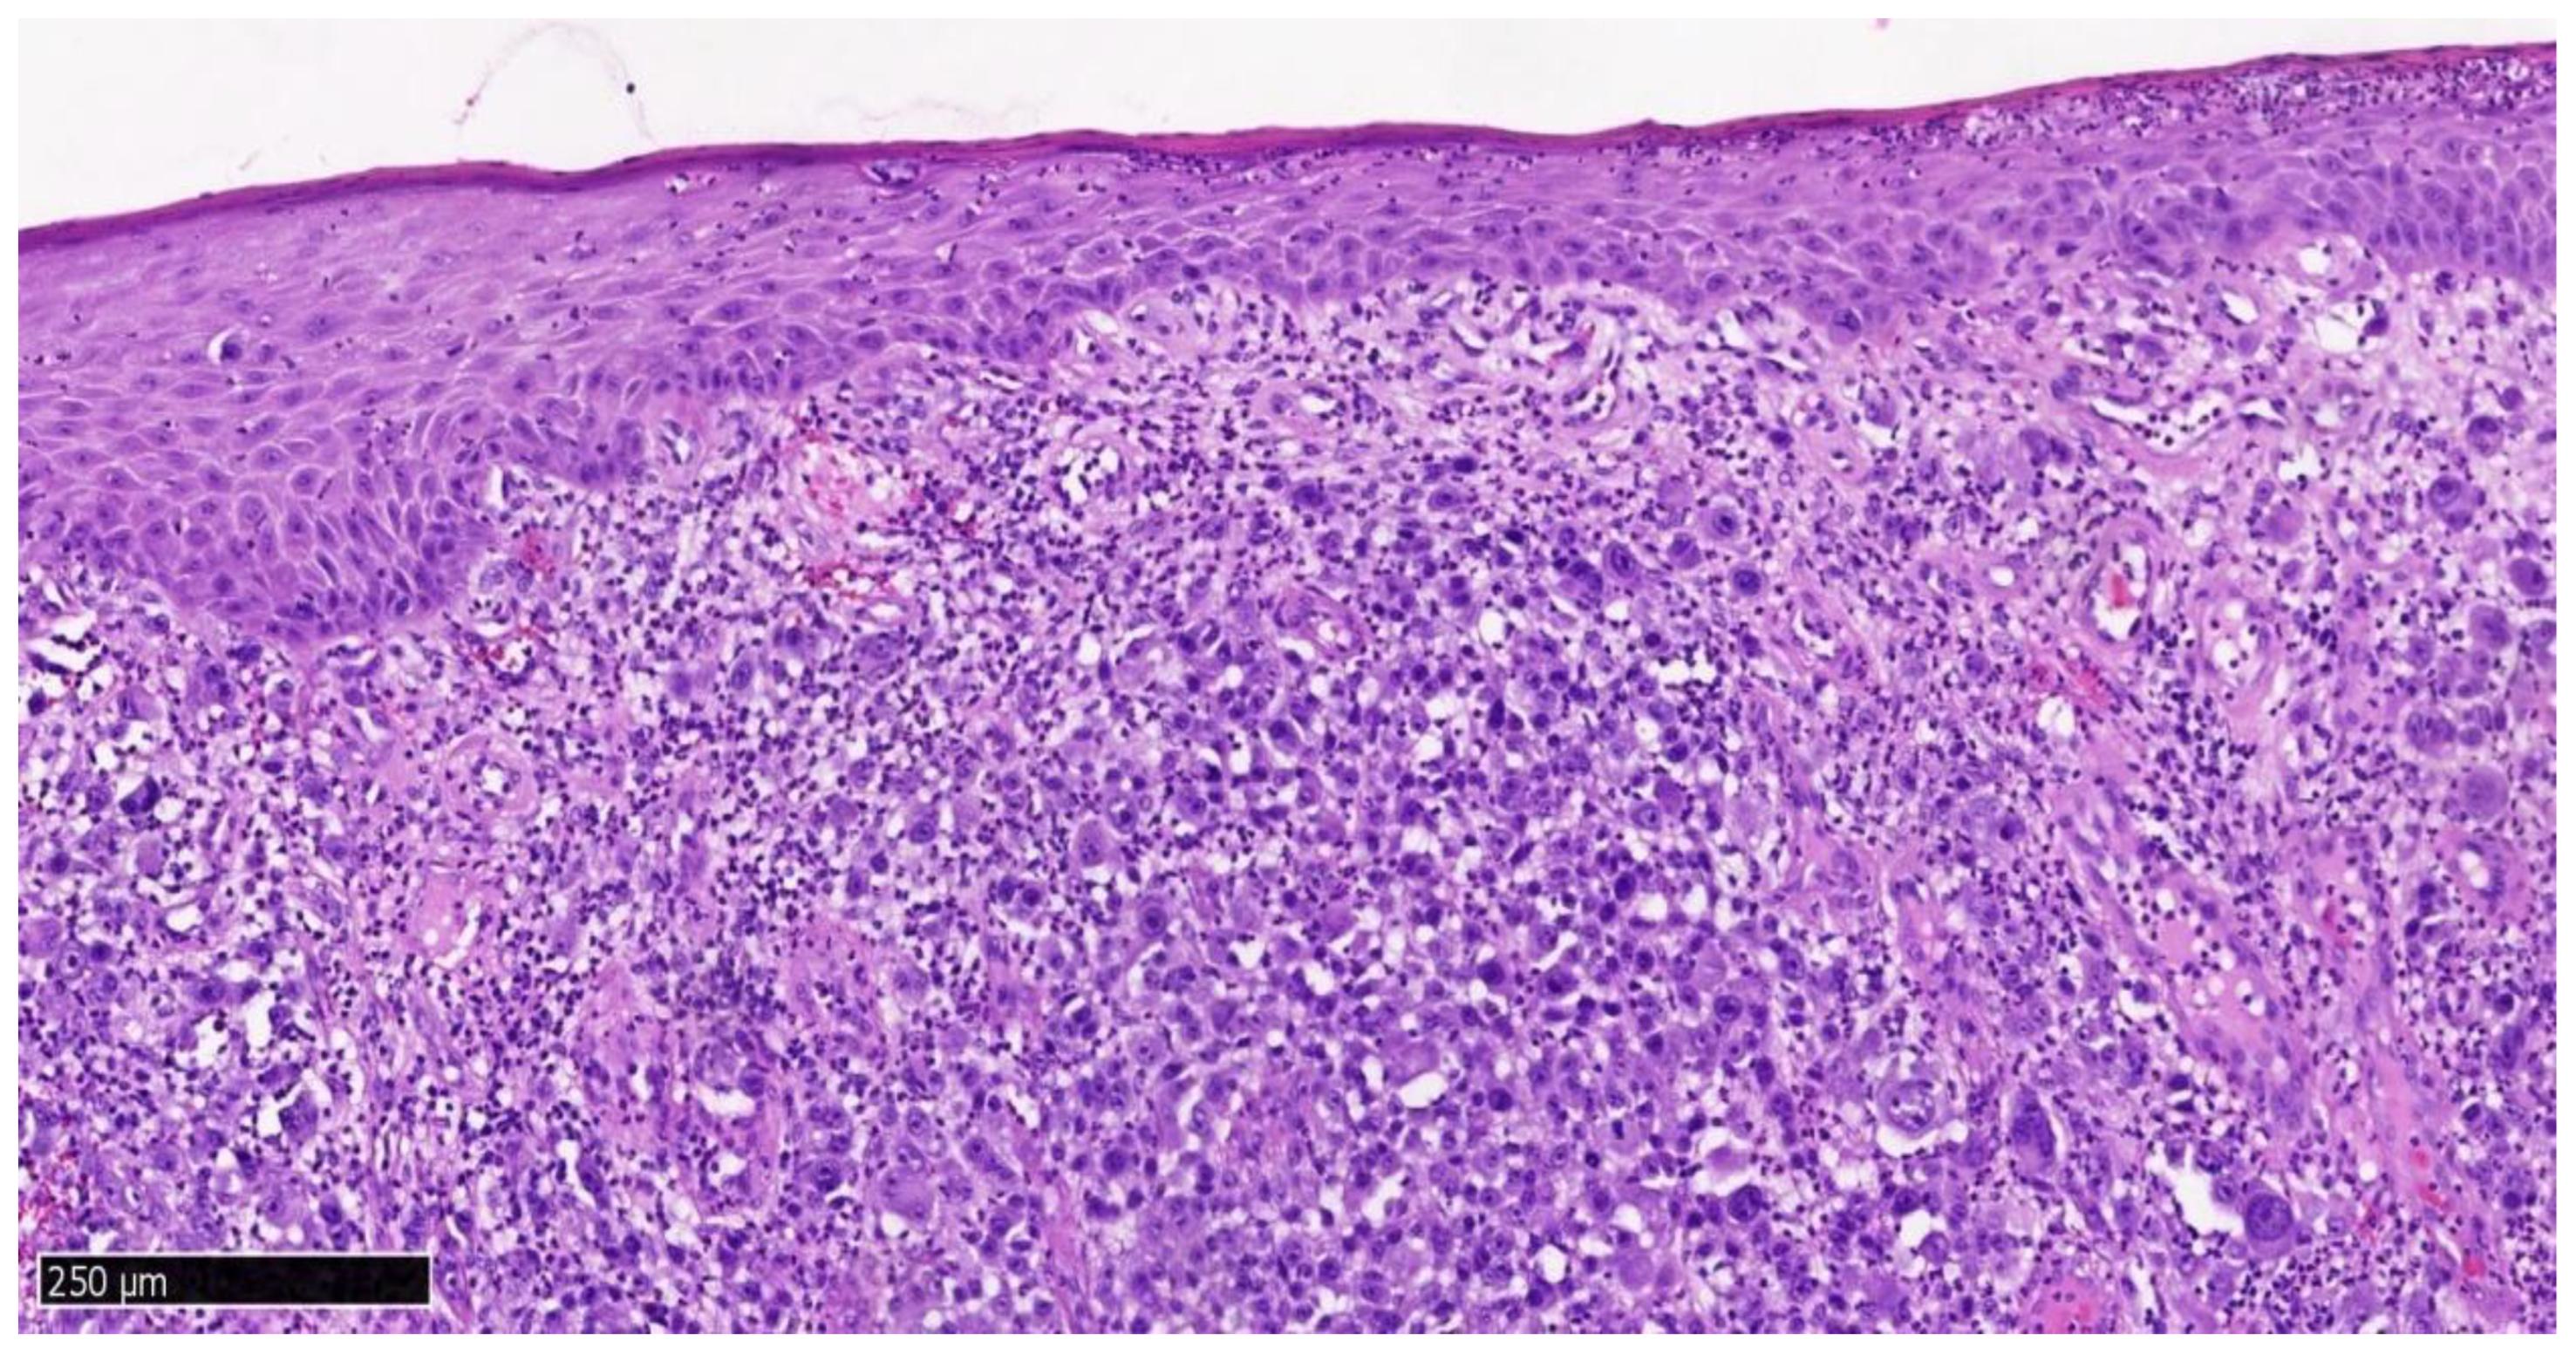

2. Case Presentation

| Step 5: Histopathological and Immunohistochemical Analysis | |

| Standard H&E staining. | |

| Immunohistochemistry: S100, SOX10, HMB45, Melan-A, Ki-67. | |